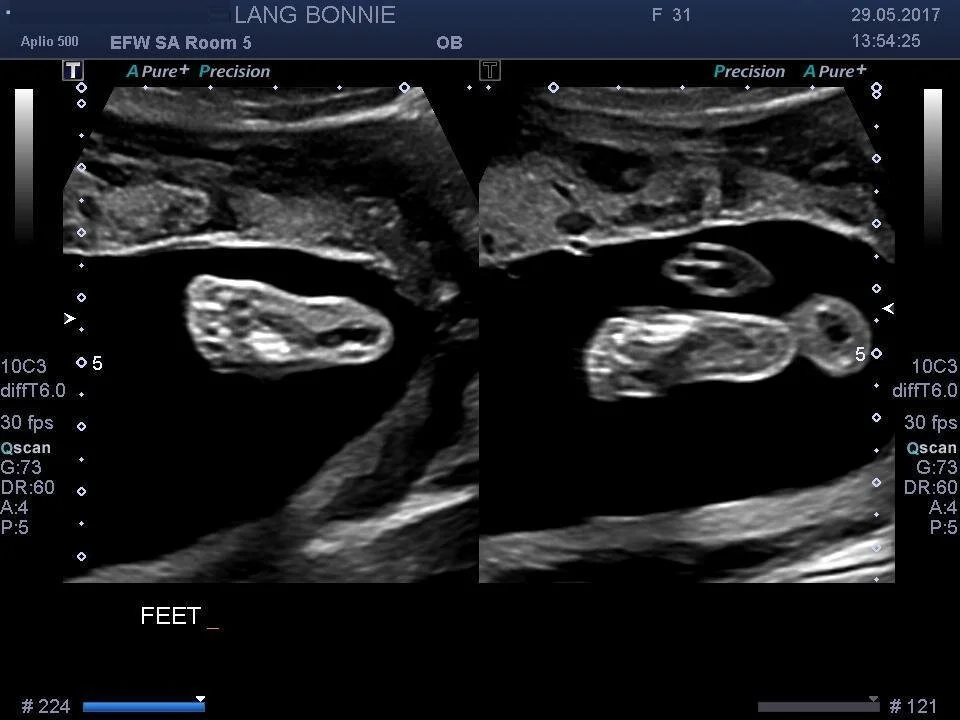

I mean, that babe is really growing! Sometimes I look down at my expanding belly and think, “Is there REALLY something in there that’s progressing and full of life?” – it’s still hard to believe this is our reality and daily we are grateful for this little guy (or girl – we aren’t finding out!). The ultrasound showed us the babe’s cerebellum, spine, fingers and toes, four chambers of her beating heart, and a very clear thumbs up. Love it!

Too cool! Love that outline of the leg!

And two little feet…kicking away at the camera.